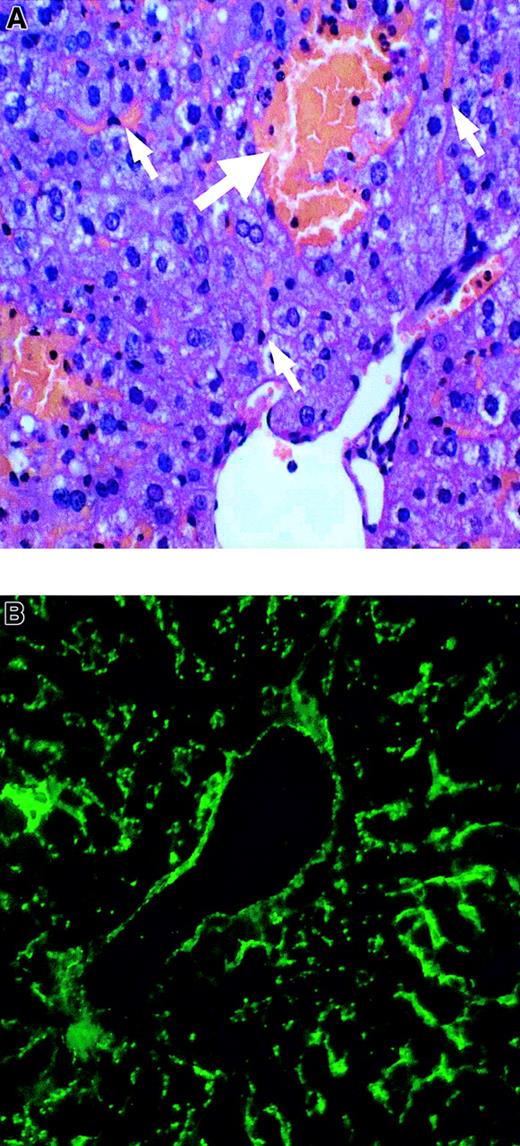

Liver, spleen, kidney, and lung tissues from the control and AOM groups were evaluated histologically. Liver sections from the AOM-30 and AOM-50 groups displayed moderate and severe multifocal necrosis, respectively, with apparent sparing of liver sinusoidal endothelial cells (Figure 1A). Hepatocellular necrosis was not evident in the AOM-15 and saline control tissues. Spleen, kidney, and lung tissues from mice in all groups appeared normal (not shown). VWF protein was detected in control and AOM-50 mice by immunofluorescence. AOM-50 mice displayed intense staining for VWF antigen within the vascular and sinusoidal endothelium (Figure 1B). This result also is consistent with the proposal that AOM is specifically toxic to hepatocytes.22

Liver histology and VWF staining in AOM-induced FHF.

(A) Paraffin section AOM-50 mouse liver stained with hematoxylin and eosin and visualized by light microscopy. White arrows denote liver sinusoidal endothelial cells. Severe necrosis is identified by the bolded arrow. (B) Frozen section of AOM-50 mouse liver revealing staining of VWF in large vessel and sinusoidal endothelium by FITC immunofluorescence. Original magnification × 200 in panels A and B.